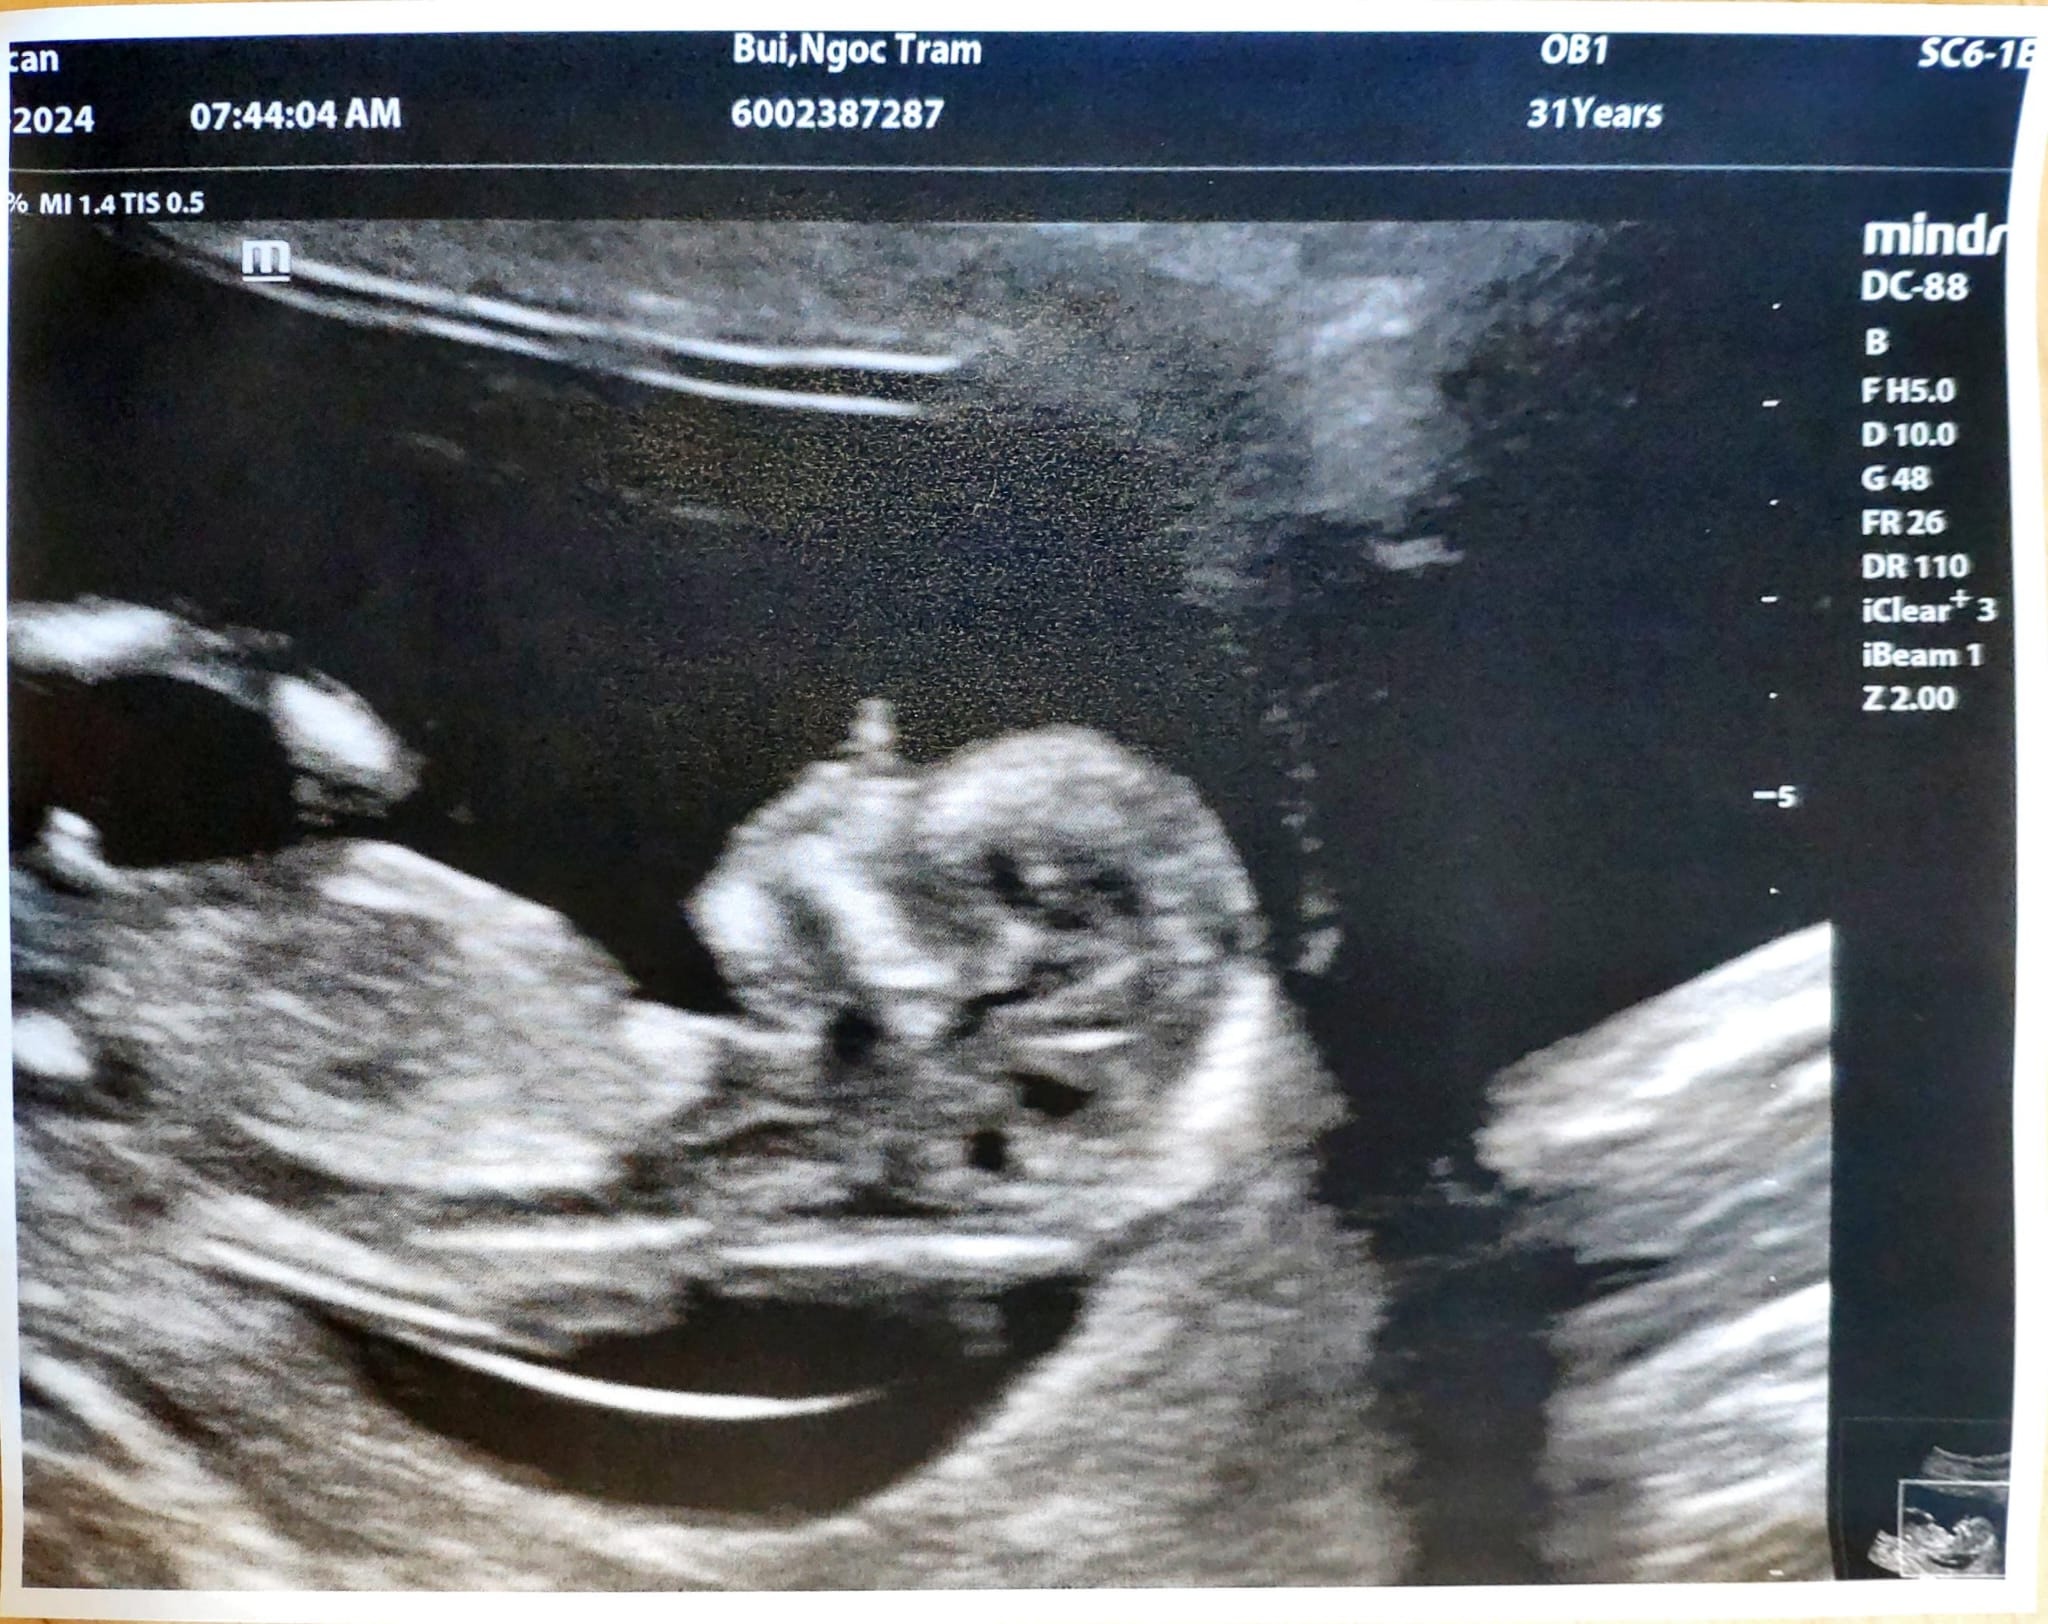

Ultrasound 4 Jan 2024

Sáng sớm 7.30 đã lái xe sang tận New Hamburg để siêu âm con.

Tin vui là con mình khoẻ, con đã có hình hài rồi đây này, nhìn là thương liền.